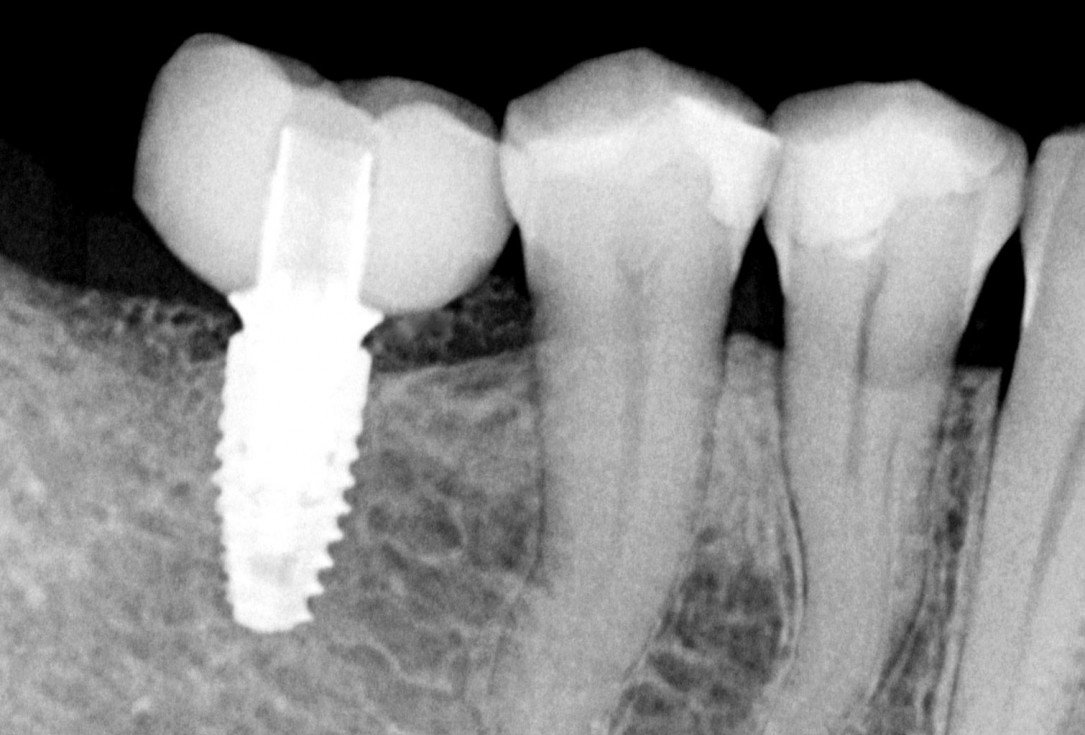

Three implants placed in a narrow posterior mandible